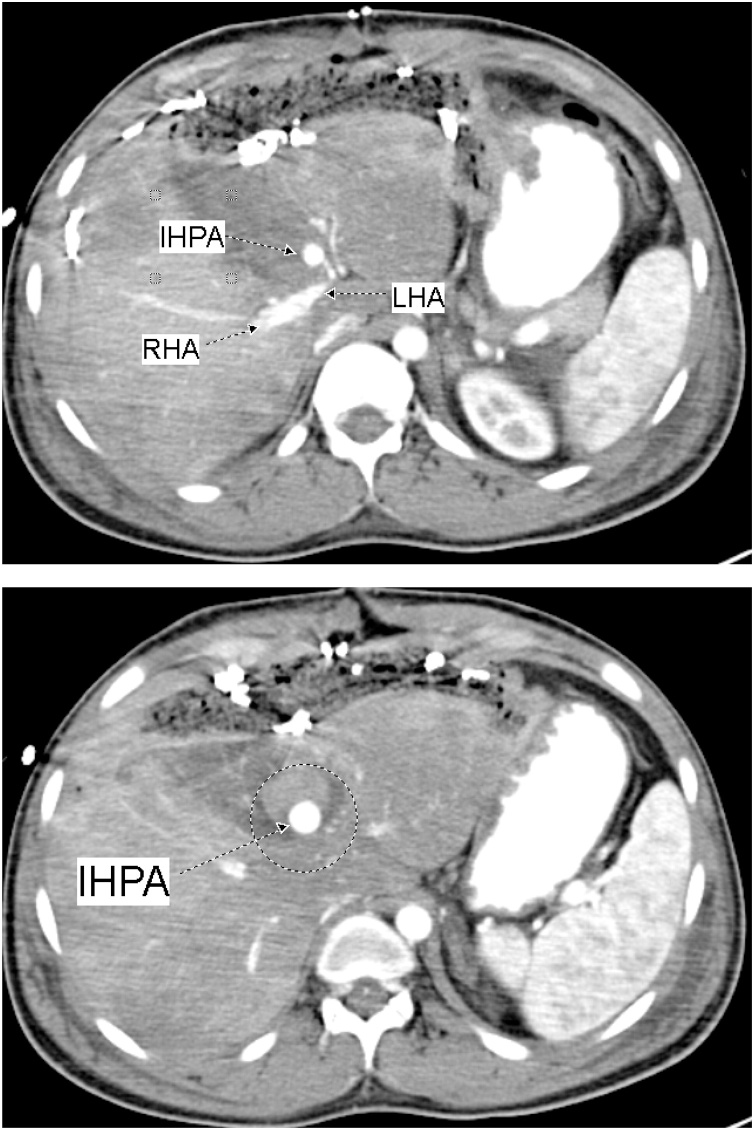

Fig. 2.

CECT Abdomen showing the Intra-Hepatic Pseudoaneurysm; IHPA, emerging from a branch of Left Hepatic Artery; LHA. The lower figure shows the IHPA surrounded by the hematoma (within the circle).